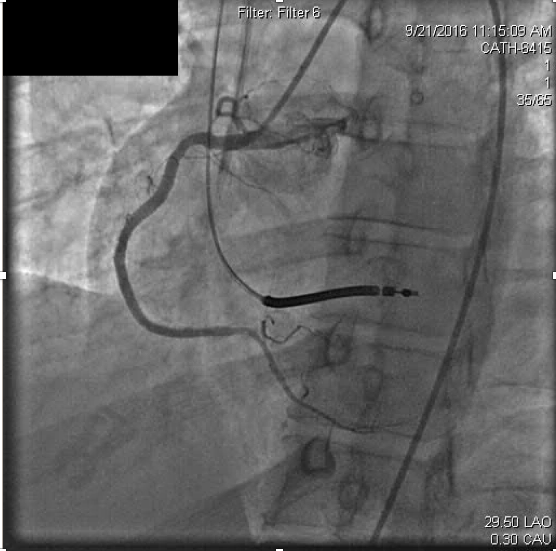

Myocardial infarctionin patients under the age of 45 is considered rare occurring in approximately 6-10% of the general population. In many cases, premature coronary atherosclerosis plays an important causative role, however about 20% of young adult coronary thrombosis can be attributed to hypercoagulability. In this article, we present a 43 year old patient with recurrent coronary thrombosis. While an initial presentation of acute myocardial infarction appeared driven by common re-thrombosis and acute stent thrombosis revealed a hypercoagulable state. This case highlights challenges in management of acute myocardial infarction and hypercoagulable states. It emphasizes the vigilance that must be exercised in generating differential diagnoses for coronary thrombosis.References